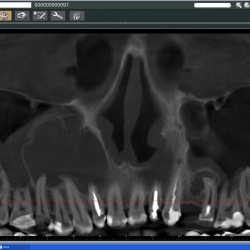

Пациент направлен на рентгенографию придаточных полостей носа оториноларингологом.

Пациент направлен на рентгенографию придаточных полостей носа.

Пациент направлен на рентгенографию придаточных полостей носа с профилактической целью ( по поводу операции на глазном яблоке).Фрагменты с увеличением.

Направлен отоларингологом 4